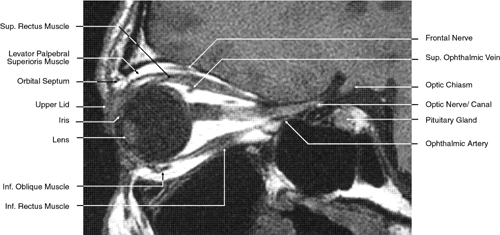

The globe is shown in Figure 12. The orbit and periorbital structures are shown in Figures 13 through 16, and the optic canal is shown in Figures 17 through 26. The cavernous sinus and optic chiasm are shown in Figures 27 and 28, and the posterior visual pathway and cranial nerves are shown in Figures 29 through 33.

Fig. 26. T1-weighted magnetic resonance imaging; sagittal image through optic nerve.